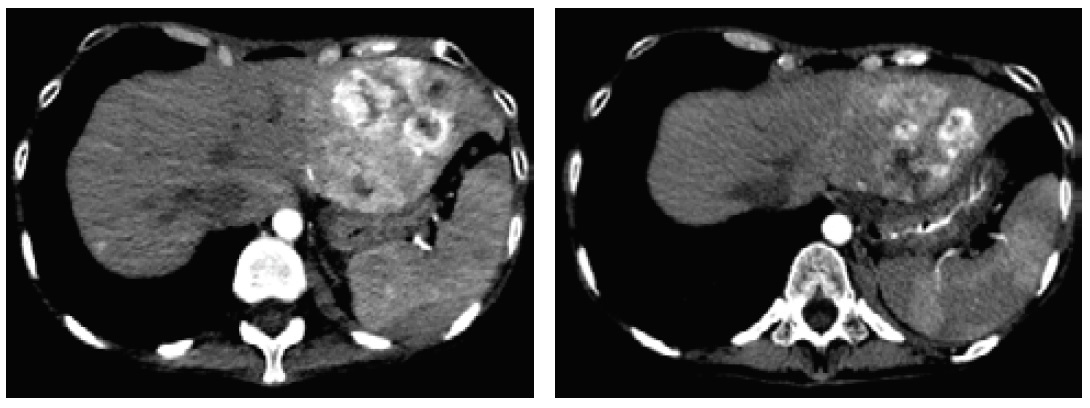

After 3 months of medical therapy, she gained 4.5 kg with improvement of the Necrolytic Migratory Erythema (Figure 3). On repeat CT scan, there was a decrease in the size of the inhomogenous mass in the left hepatic lobe (4.4 x 5.8 x 5.2 cm from 7.6 x 7.1 x 6.6 cm) (Figure 4).

Figure 4. Decreased size of the inhomogenous mass in the left hepatic lobe.